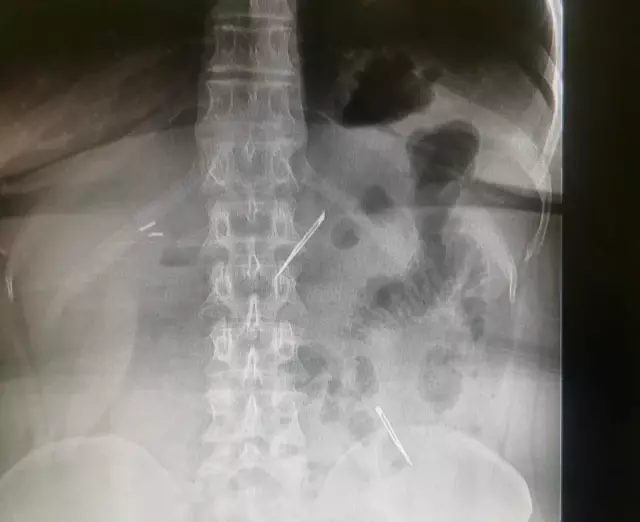

Sağlık Bilimleri Üniversitesi Ankara Atatürk Sanatoryum Eğitim ve Araştırma Hastanesi'ne mide ve karın bölgesinde aşırı ağrı şikayeti ile müracaat eden 46 yaşındaki D.E.'nin yapılan tahlil, tetkik ve çeşitli görüntülemelerden sonra bağırsak kısmında 2 adet neşter olduğu tespit edildi. Genel cerrahi kliniği tarafından zorlu bir ameliyat sonrasında neşterler kadının vücudundan çıkarıldı. 46 yaşındaki D.E. neşterleri nasıl yuttuğunu bilmediğini tahminen ekmek ile birlikte yutabilmiş olabileceğini ifade etti. Ameliyatı gerçekleştiren Sağlık Bilimleri Üniversitesi Ankara Atatürk Sanatoryum Eğitim ve Araştırma Hastanesi Genel Cerrahi Kliniği Eğitim ve İdari sorumlusu Prof. Dr. Hakan Buluş ise hastanın yoğun şikayetleri üzerine çektikleri röntgen sonrasında 2 adet neşteri görünce şaşkına uğradıklarını söyledi.

Hastanın şikayetlerinin artması üzerine gerçekleştirilen tetkiklerde 46 yaşındaki kadının karın bölgesinde 2 adet yabancı cisim olduğunu tespit ettiklerini, detaylı inceleme sonucunda bu cisimlerin neşter olduğunu fark ettiklerini belirten Prof. Dr. Buluş, "Yaklaşık 10 gün önce kliniğimize karın ağrısı ve bulantı şikayetleri ile başvurdu. Bizim yaptığımız fiziki muayene ve tetkiklerinde hastanın direkt karın grafisinde 2 adet yabancı cisim olduğunu tespit ettik. Aslında yabancı cisim bizim güncel grafiğimizde sık karşılaştığımız bir durum değil, fakat nadir de olsa görebildiğimiz bir patoloji.

Biz de bunun üzerine ayrıntılı değerlendirmeler ve tetkikler yaptık. Sonrasında 2 adet yabancı cismin bistüri (neşter) ile uyumlu olduğunu gördük. Bunun üzerine hastanın şikayetlerinin de artması üzerine, ameliyat kararı verdik. Yaptığımız ameliyatta ince bağırsağın yaklaşık 180'inci santimetresinde bu yabancı cisimlerin olduğunu tespit ettik. Bunun üzerine ameliyatla bunları çıkarttık. Hastamızın sağlık durumu şuan gayet iyi. Ameliyattan sonraki üçüncü günü. Şuan bir problemi yok, inşallah birkaç gün içerisinde şifa ile taburcu etmeyi düşünüyoruz" şeklinde konuştu.

Çıkardıkları cismin, neşterin normalde ameliyatlarda kullanılan bir malzeme olduğunu söyleyen Prof. Dr. Buluş, "Çıkardığımız yabancı cisimler bizim ameliyatlarda sıkça kullandığımız 11 numara dediğimiz bir bistüri tipi. Ebatları da yaklaşık 4 santime yarım santim ebatlarında. Ucunun sivri olması nedeniyle ince bağırsak mukozasına saplanarak enflamasyon ve bir karın ağrısı yapması, sonrasında da ağrı şikayetlerinin artmasına neden olmasından dolayı ameliyat kararı verdik" diye konuştu.